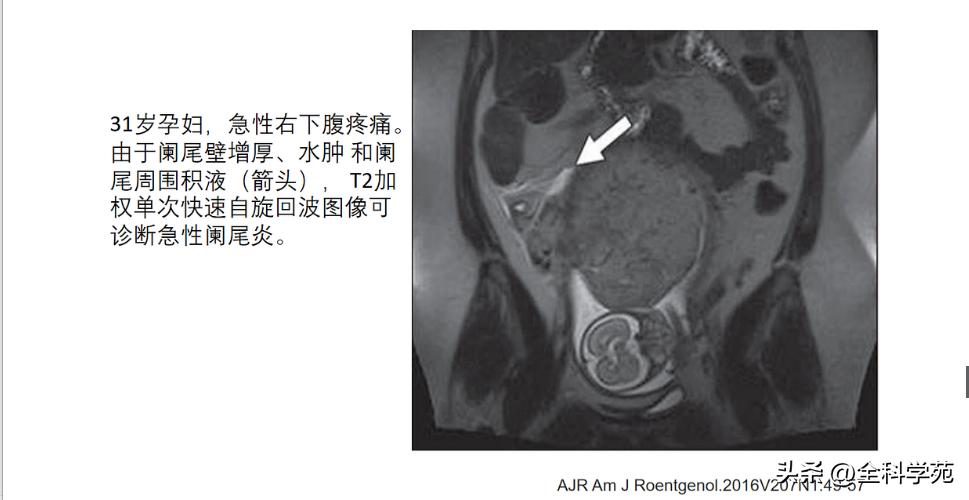

▪ 最常用检查方法: 螺旋CT和腹部超声.CT检查敏感性91-98%;特异性75-93%,MRI检查应用于小儿和妊娠期妇女

▪ 推荐: US适用于婴幼儿,儿童,孕妇和偏瘦病人,以及有基础病的;CT在US无法显示的情况下使用,平扫即可,情况允许可增强:MRI孕妇、儿童适用。

MRI: T1低信号,T2高信号,DWI: 扩散受限

6-10 mm 伴阑尾壁增厚、壁明显强化,周围脂肪间隙模糊或分层(靶征或牛眼征,表明粘膜下水肿的液体含量vs 气体含量

◆ 阑尾周围脂肪密度增高/模糊与腹腔其他部位的脂肪比较,CT表现为脂肪密度增高,T2压脂为高信号